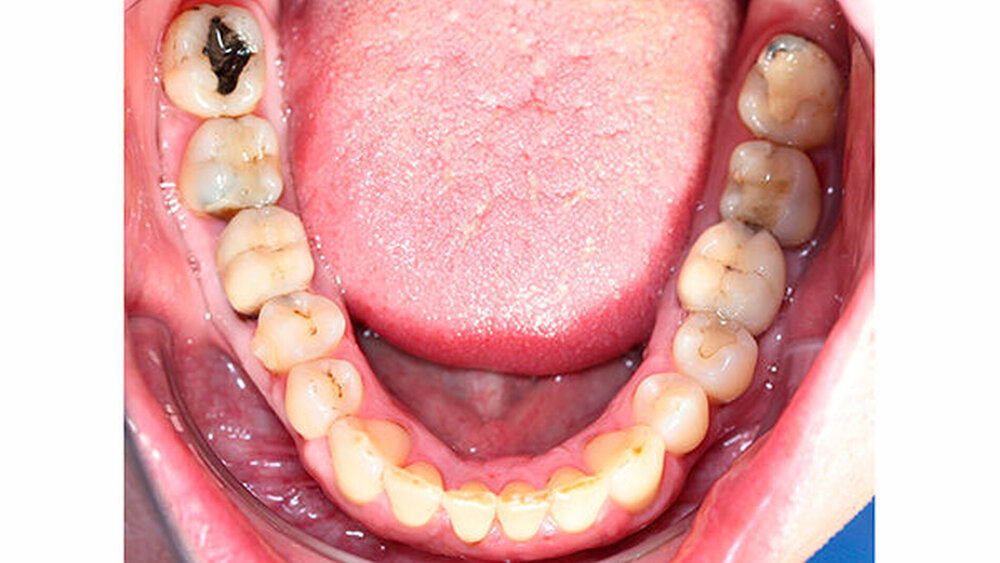

Intraoral zeigte sich ein bereits konservierend versorgtes permanentes Gebiss mit aktivem und inaktivem kariösen Geschehen. Große Anteile der Zahnhälse lagen nach Zahnfleischrückgang in Kombination mit Knocheneinbrüchen frei. Zahn 27 wurde bereits extrahiert.

Röntgenologisch stellte sich im Orthopantomogramm der bereits intraoral ersichtliche horizontale und vertikale Knochenabbau mit Attachmentverlust an einzelnen Zähnen dar. Die Erhaltungswürdigkeit einzelner Zähne war aufgrund des starken Knochenverlustes beziehungsweise der Beeinträchtigung des Halteapparates als kritisch zu beurteilen.

Zudem wurde die Diagnose einer Parodontitis gestellt, die eine Rücküberweisung an den Hauszahnarzt erforderlich machte (Abbildung 2).